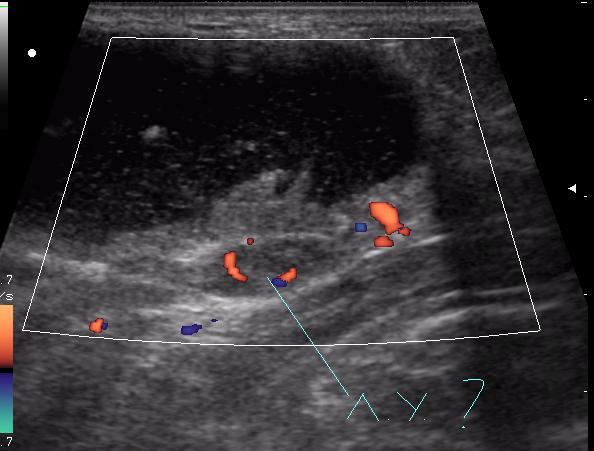

В клинику обратилась мать 11-летней девочки с жалобами на появление припухлости в подключичной области справа. Впервые заметили в феврале. За 4 месяца не интенсивный рост образования, с переходом на переднюю поверхность плеча, где кожа над ним на ограниченном участке (1.5-2см) имеет багрово-синюшную окраску.

Из анамнеза - ДТП осенью прошлого года.

(с д-зом Гематома(?) направлена на УЗИ)

достоверной связи с мышцами не увидела. Но на задней проекции включения определяется солидное образование. это может быть лимфоузел?